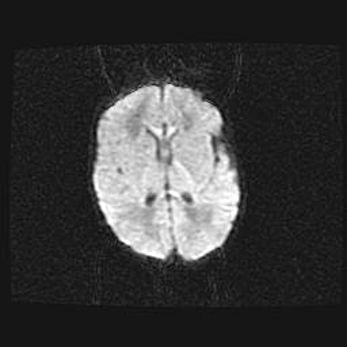

Лейкомаляция с кистозно-глиозной дегенерацией головного мозга.

Возраст: 2 месяца 25 дней

Вес: 6400 г

Окружность головы: 40 см

Срок гестации: 41 неделя

Лейкомаляцию относят к ишемически-гипоксическим повреждениям головного мозга, диагностируемым у новорожденных. При лейкомаляции в головном мозге обнаруживают очаги некроза, возникшие после тяжелой гипоксии и нарушения кровотока. В процессе морфогенеза очаги проходят три стадии: 1) развития некроза, 2) резорбции и 3) формирования глиозного рубца или кисты. Перивентрикулярная лейкомаляция (ПЛ) встречается примерно в 12% случаев среди новорожденных, обычно – у недоношенных детей, причем, частота ее зависит от массы, с которой младенец появился на свет. Наибольшее число малышей страдает лейкомаляцией, если масса при рождении 1500-2500 г.